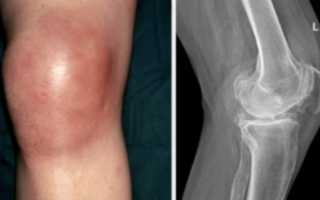

Симптоматика

Артрит коленного сустава проявляется рядом характерных признаков:

- Ограничение подвижности и скованность (это связано с выраженным отеком и накоплением жидкости в суставной полости);

- Боль в передней части колена, которая усиливается при физической нагрузке;

- Появление отечности в области коленного сустава;

- Накопление экссудата в суставной полости;

- Покраснение кожи вокруг пораженного участка;

- Локальное повышение температуры в области поражения, которая может достигать 10 см в диаметре;

- Изменение формы конечности, она становится веретенообразной;

Каковы основные методы диагностики артрита коленного сустава?

Диагностика артрита коленного сустава обычно включает физический осмотр, анализ медицинской истории пациента, рентгенографию для оценки состояния суставов, а также анализы крови для выявления воспалительных маркеров и других заболеваний, таких как подагра или ревматоидный артрит.